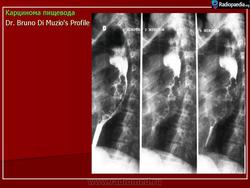

Рак пищевода

Fig.6.: Esophageal tumor.